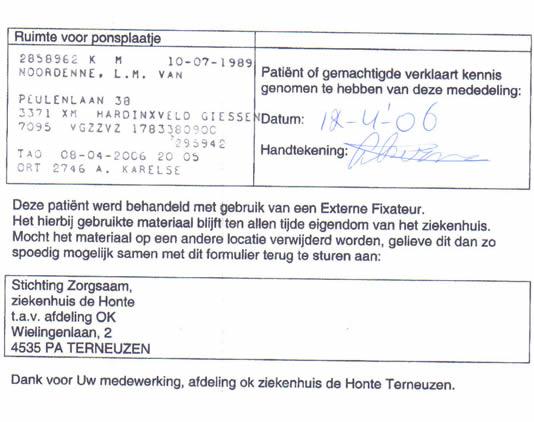

Nadat we nog even in Terneuzen een kadootje gekocht hadden voor kamergenoot Annemarieke, die nog 3 maanden in het ziekenhuis moet blijven, gaf Leonard ons dit formuliertje.

Wat blijkt, de Externe Fixateur (de verstelbare beugel) die gebruikt is om Leonard zijn voet te stabiliseren kost € 3000,– Het ziekenhuis is bezorgd, omdat men niet verwacht dat het Ziekenhuis in Dordrecht ‘m terug zal geven. KASSA!!! Men hoopt nu dat wij ook een oogje in het zeil zullen houden.